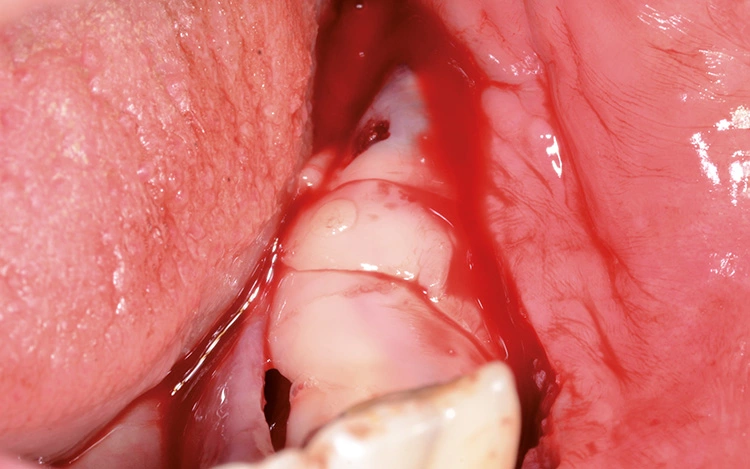

Implantation: 7 Monate nach Augmentation

Trotz der schlechten, hart- und weichgewebigen Grundvoraussetzungen konnte der Kieferkamm zufriedenstellend rekonstruiert werden. Die Augmentation des kombinierten, horizontalen und vertikalen Defekts mit Yxoss CBR®, Geistlich Bio-Oss®, Geistlich Bio-Gide®, autologem Knochen und PRF ermöglichte die Implantation mit hoher Primärstabilität in den rekonstruierten Bereich.